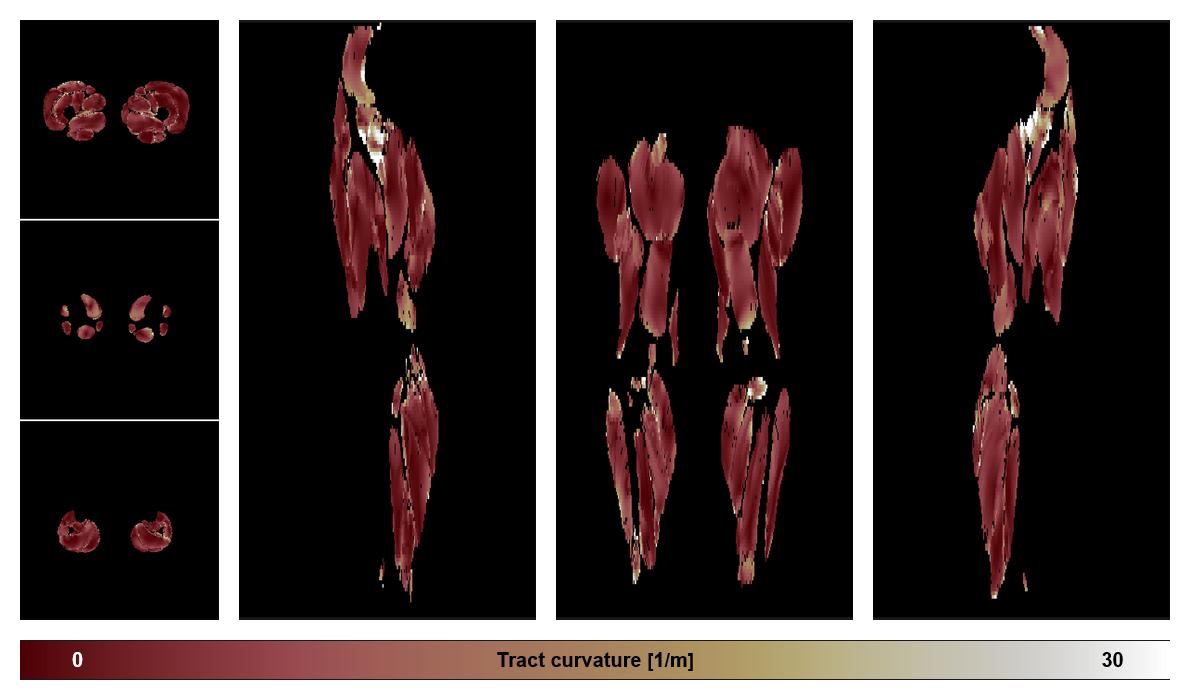

• Muscle fiber curvature map

Muscle fiber tract curvature map based on whole leg DTI based fiber tractography.